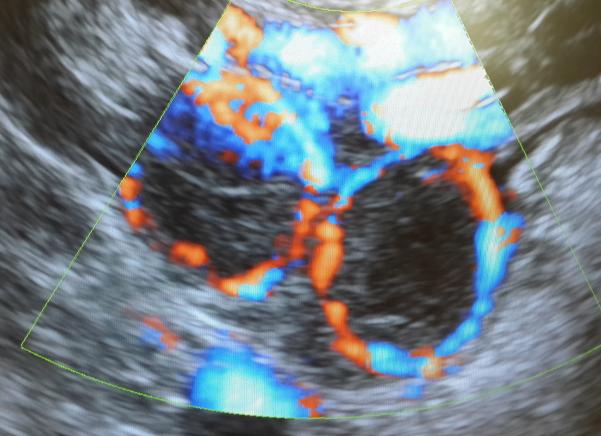

Нормальным считается, когда лютеиновая железа проникает только в один яичник, что и должна показывать диагностика. На экране монитора всегда видно, как выглядит желтое тело на УЗИ. Это неоднородное образование круглой формы, имеющее желтый цвет, которое появляется в так называемом доминантном яичнике, где лопается фолликул. Так созревает яйцеклетка, из которой потом развивается плод.

Иногда УЗИ показывает наличие нескольких желтых тел в одном яичнике, что свидетельствует о наступлении так называемой многоплодной беременности. Если произошло оплодотворение одной яйцеклетки, а из нее развиваются 2 плода, тогда родятся однояйцовые близнецы.

Результатом оплодотворения двух яйцеклеток будет появление на свет разнояйцовых близнецов. Два желтых тела в одном яичнике и появление близнецов встречается раз в 80-90 случаев.

Два желтых тела могут появиться и в двух разных яичниках, что тоже будет говорить о возможном наступлении многоплодной беременности. Но два желтых тела не всегда говорят о том, что развитие нескольких плодов станет возможным. Иногда беременность наступает только в одном фолликуле, поэтому вторая железа отмирает.

Два желтых тела — это нормальное состояние, хотя на месте второй железы может образоваться киста. Поэтому врач внимательно изучает наличие двух желтых тел, чтобы вовремя обнаружить патологии или правильно вести многоплодную беременность.